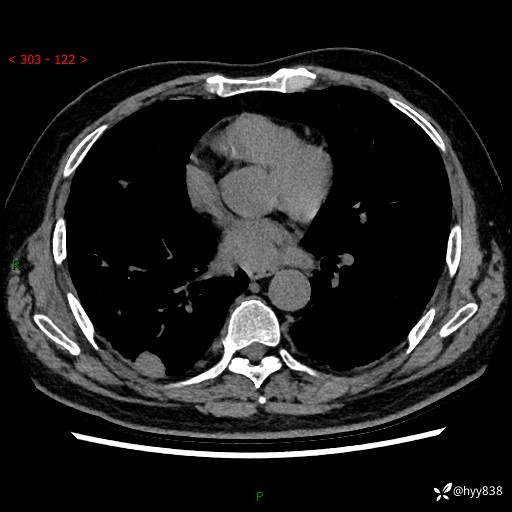

71岁/男,咳嗽伴气促半月。一年前肺手术史,又见两个结节,穿刺结果意外---结果公布~

【现病史】:患者半月前无明显诱因出现咳嗽、咳痰,为白色粘痰,无明显加重与缓解因素,伴气促,无发热,无大量脓痰,无胸痛、咯血,无哮鸣音,到我院就诊,胸部CT示右肺结节增大,并口服药物治疗无明显好转,具体用药不详,为求进一步治疗随来我院,经门诊以“孤立性肺结节”收入我科。 病程中患者精神、饮食可,睡眠不佳,大小便正常,体力下降,体重未见明显下降。

[既往史]:2022-06于当地第一人民医院确诊慢阻肺,现规律使用杰润(1次/日);2023-04-06于当地市第一人民医院行胸腔镜右肺上叶楔形切除术+右肺上叶切除术+淋巴结清扫术+胸膜黏连松解术,确诊为右肺鳞癌 pT2aN0M0 Ib期

【检查】:胸部CT平扫+增强